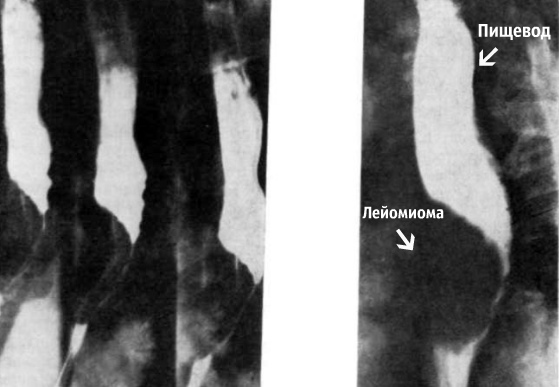

Диагностика заболевания осуществляется рентгенологическим и эндоскопическим путями, что дает возможность визуализировать онкологический очаг и определить лечебную тактику. Своевременное удаление новообразования позволяет снизить риск осложнений и увеличить продолжительность жизни.

При контрастной рентгенографии с барием выявляются признаки онкообразования в виде дефекта наполнения и расширения пищевода на данном участке. При обзорной рентгенографии визуализируется тень опухоли.

Множественные узлы лейомиомы могут давать перекрещивающиеся контуры, такие как при кистах и других видах опухолей. Для подтверждения диагноза проводится эзофагоскопия, благодаря которой визуализируются образования, оценивается состояние слизистой оболочки и иссекается материал для биопсии.